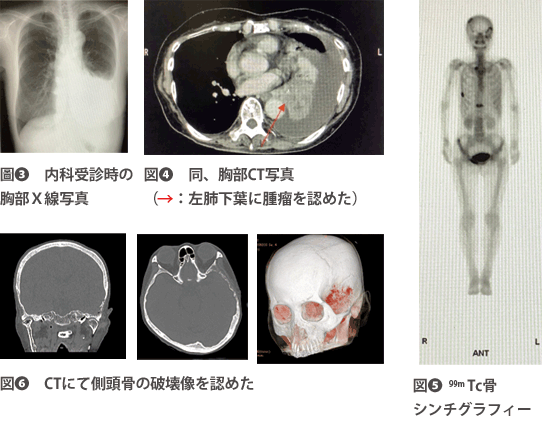

左肺腺がん(Stage IV)、多発骨転移(左側頭骨、右恥骨)、両副腎転移。

本症例は、肺がんの側頭骨転移症例である。紹介元の耳鼻科からは顎関節症の疑いにて精査加療の依頼であったが、当科初診時の所見より、耳下腺疾患と顎関節疾患はいずれも否定的と考えた。血液所見および側頭部の自発痛が続くことから巨細胞性動脈炎を疑い、総合内科に対診依頼を行ったところ、全身CT撮影により肺がんとその多発骨転移が判明した(図❸~❻)。病理検査では、胸水のセルブロックより腺がんの診断となった。

また、頭部皮膚腫瘤の生検においても、腺がんの病理組織診断を得た。呼吸器内科にて入院加療が行われたが、その後不幸な転帰を辿ることとなった。